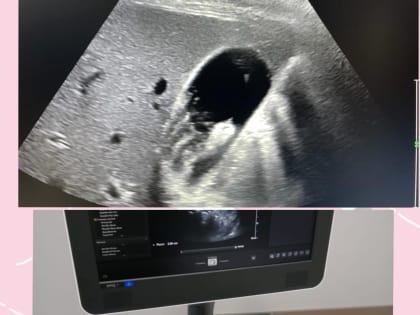

Желчный пузырь это...

Как вы думаете, что представлено на снимке? Это мотор нашего желудочно-кишечного тракта - желчный пузырь!